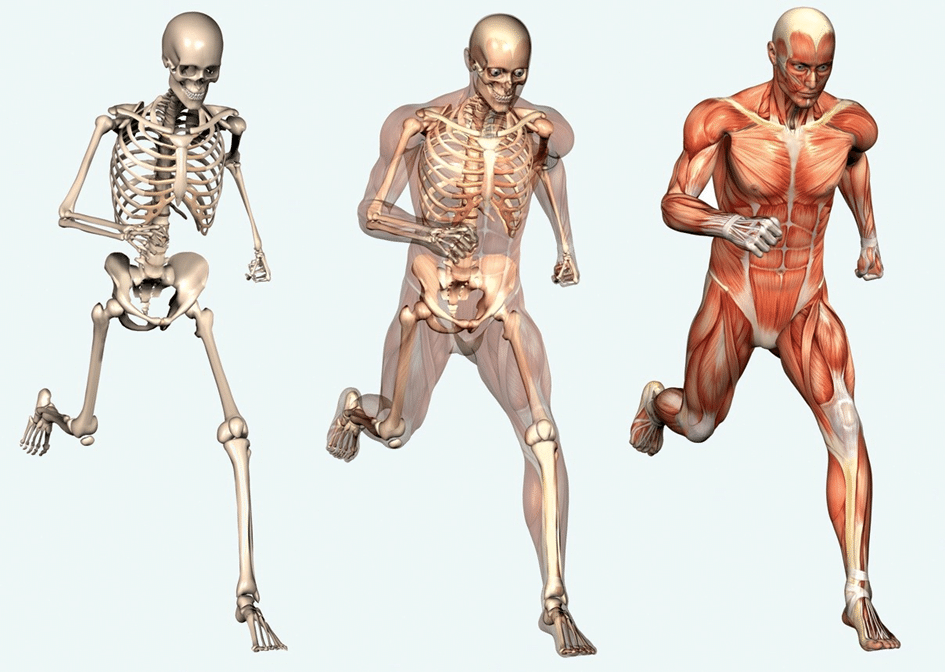

L'ostéopathie est une médecine douce / thérapie manuelle, visant à rétablir la mobilité de l'ensemble des structures composant notre corps.

Elle repose sur la connaissance parfaite de l'anatomie afin d'évaluer les liens possibles entre plusieurs zones corporelles et de définir l'origine d'une ou plusieurs douleurs.

L'ostéopathie vise à redonner la mobilité dont le corps à besoin

pour éliminer les contraintes qui nuisent à celui-ci.

Douleurs musculo-squelettiques

Ce sont les douleurs articulaires ou musculaires que l'on peut ressentir au cours d'une journée.